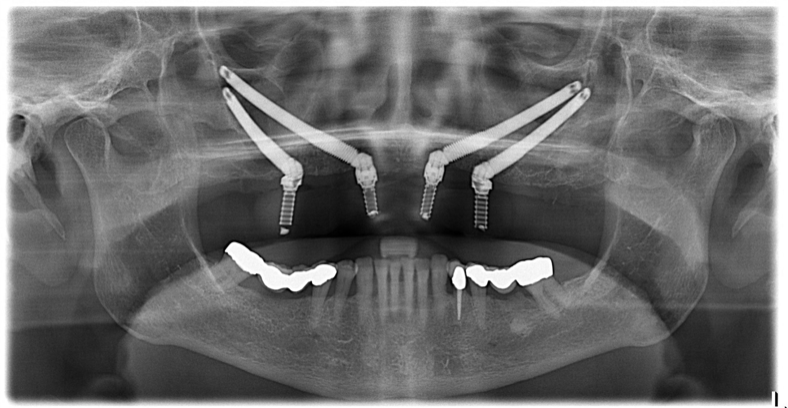

Per poter procedere con l’intervento a carico immediato è necessaria una valutazione del Prof. Giulio Gasparini specialista in Chirurgia Maxillo Facciale che mediante una prima visita iniziale, eseguendo un’ anamnesi ed esami radiografici preliminari, è in grado di determinare se ci sono le condizioni favorevoli dell’osso, in cui verranno inseriti gli impianti. Da questo momento l’esecuzione degli impianti a carico immediato e alla consegna dei vostri nuovi denti è solo una questione di poco tempo.

II fase o tempo dell'inserimento degli impianti: in questo tempo terapeutico si procede all’inserimento di impianti in titanio nelle zone edentule delle ossa mascellari e/o mandibolari. Grazie alla particolare tipologia di impianti specifici e al corretto posizionamento degli stessi, è possibile procedere direttamente con la fase protesica. L’intervento sarà completamente indolore grazie anche all’ausilio della sedazione cosciente (previa valutazione medica del nostro anestesista).

Abbiamo una esperienza Implantare trentennale. Abbiamo utilizzato tutti i tipi di impianti esistenti in commercio a cominciare dagli impianti iuxtaperiostei fino a giungere agli impianti Zigomatici e dai miniimpianti con una percentuale di successo superiore al 98%. Il Prof. Giulio Gasparini ha organizzato Corsi e Master Universitari nei quali ha formato centinaia di odontoiatri implantologi in tutta Italia.